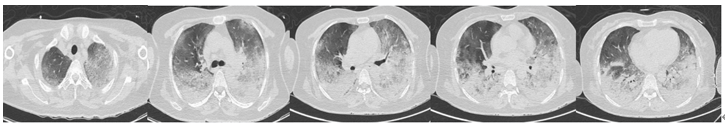

患者,女,52岁,胸闷、气喘2周,加重伴呼吸困难20小时,于2020年3月25日入院。“皮肌炎”病史5个月,规律口服甲泼尼龙、环孢素。胸部CT可见弥漫磨玻璃改变,白肺。第一时间送BALF mNGS,结果回报耶氏肺孢子菌(PCP)(序列数27115),人类疱疹病毒5型(CMV)(序列数14472),曲霉(序列数3),涂片查到耶氏肺孢子菌,病原学最终诊断:PCP+CMV+曲霉混合感染。给予磺胺+卡泊芬净+更昔洛韦联合治疗,并予以VV-ECMO、间歇正压通气+俯卧位通气(IPPV+PPV),最终患者痊愈出院。

治疗前胸部CT

治疗后胸部CT